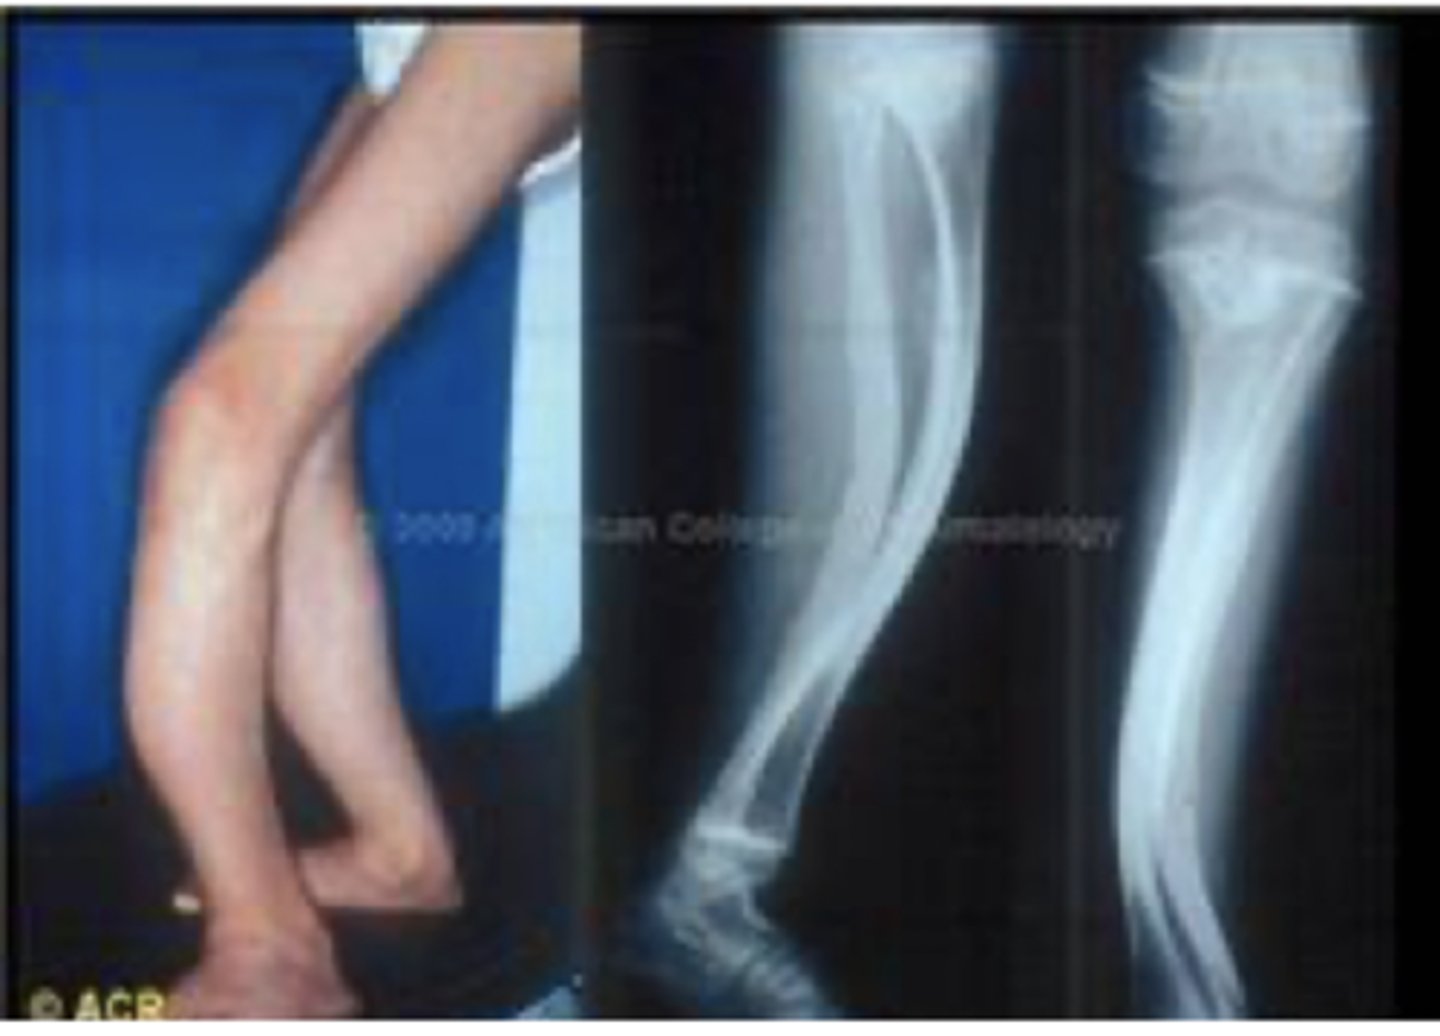

Vad är osteogenesis imperfecta?

En genetisk sjukdom orsakad av mutationer i kollagengenen som leder till defekter i benvävnaden och gör det skört